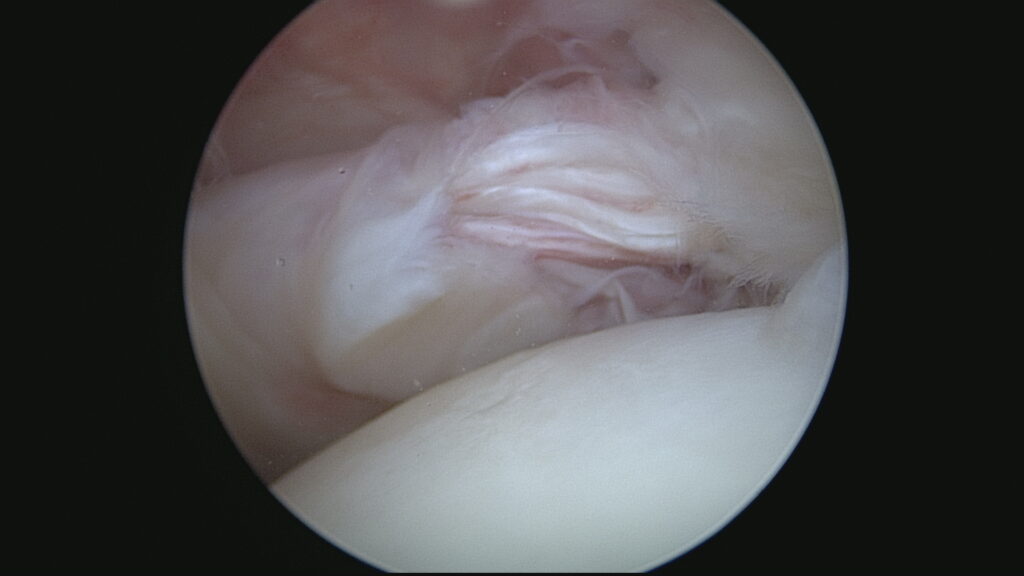

Lésion Longue Portion du Biceps (Vue 1)

Lésion Longue Portion du Biceps (Vue 2)